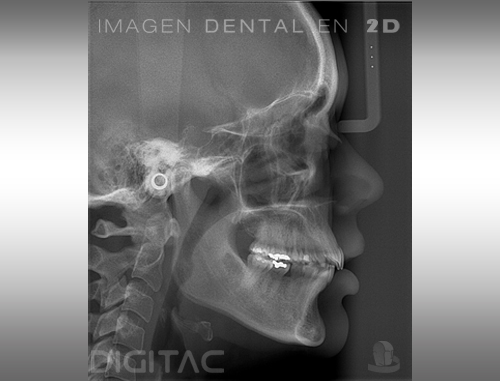

Telerradiografía lateral de cráneo [2D]

La telerradiografía lateral es una técnica radiográfica extraoral mediante la cual se obtiene una vista lateral del cráneo y las estructuras óseas de la cara.

Estas radiografías son una parte fundamental de los estudios de ortodoncia, ya que permiten medir los ángulos y proporciones de los huesos de la cara del paciente y conocer así la relación entre sus estructuras faciales. A partir de ellas se elaboran lo que se conocen como estudios cefalométricos. Es por eso que las telerradiografías son un elemento crucial en el diagnóstico y tratamiento de las maloclusiones.